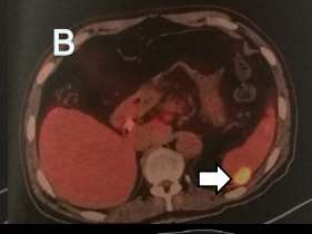

此前患者因無明顯誘因出現(xiàn)胃納下降,伴進(jìn)行性消瘦。外院CT檢查提示肝臟占位,后完善PET/CT檢查并行肝臟腫物穿刺活檢,病理提示:肝膽管細(xì)胞癌。

影像檢查

入院完善相關(guān)檢查發(fā)現(xiàn),其肝臟病灶與鄰近胃小彎、膈肌粘連、分界不清;門靜脈左支及肝左靜脈未見顯示,考慮受侵;左上腹腔前側(cè)及后側(cè)腹膜局限性增厚,考慮腹膜轉(zhuǎn)移瘤,部分病灶與鄰近左側(cè)膈肌、脾臟粘連、分界不清。

此外,腫瘤標(biāo)志物尤其是CA19-9:259.4U/ml,CA125:103.40U/ml。

以劉樹鵬副主任為首的醫(yī)療五科專家團(tuán)隊(duì)充分研討后認(rèn)為:該患者腫瘤位于肝膽管區(qū)域,大小約7.4cm*5.9cm*6.2cm,且腫瘤性質(zhì)明確,為肝膽管細(xì)胞癌。多學(xué)科會(huì)診后,考慮患者腫瘤已侵犯周圍組織,同時(shí)伴遠(yuǎn)處轉(zhuǎn)移癌,無手術(shù)切除指征,專家為其采用不可逆電穿孔消融(IRE)聯(lián)合化療方案治療。